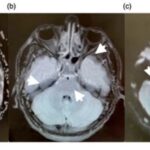

En esta investigación que se viene señalando, se puede mencionar el caso de un joven de 16 años, con alteración aguda del estado mental por inhalación de vapor de heroína. Se le efectuó una RM que evidenció hiperintensidades en T2 de la sustancia blanca simétrica difusa infratentorial y supratentorial. El diagnóstico clínico en este caso fue rabdomiólisis, que afecta predominantemente la musculatura posterior del cuello(21) (ver Imágenes 11 y 12).

Otro caso que merece ser comentado es el de un adolescente de 15 años que presentó encefalopatía y signos extrapiramidales por ingestión de metadona. La RM evidenció focos de infartos agudos en el caudado y putamen, así como infartos corticales de la línea divisoria de aguas parietales(21) (ver Imagen 13).